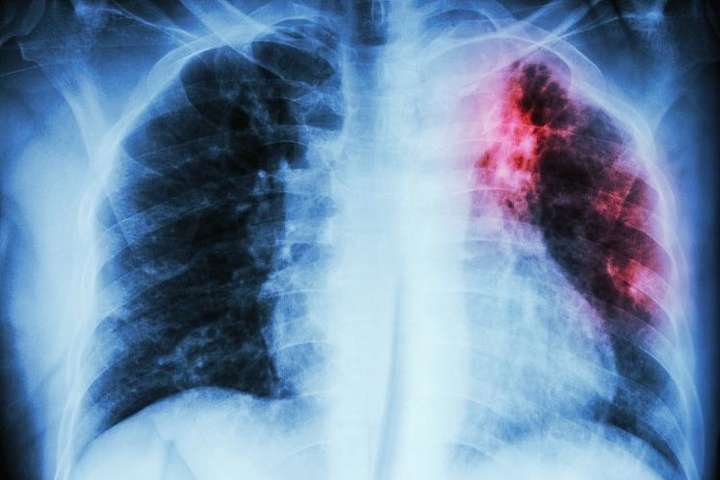

Якщо ж брати до уваги статистичні дані, то в середньому на туберкульоз хворіє 69 людей із 100 тисяч населення.

На сьогодні рівень захворюваності туберкульозом зростає, що може призвести до епідемії як в області, так і в країні загалом. Раніше такий рівень захворюваності на страшний недуг називали “африканським показником”, але сьогодні Україна займає п’яту сходинку у світі по поширенню мультирезистентного туберкульозу.